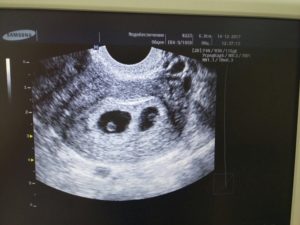

В 25% случаев из 60% удачных результатов ЭКО развивается многоплодие. Это случается по причине того, что женщине подсаживают сразу несколько эмбрионов для увеличения шансов на беременность. Иногда один зародыш не приживается, а второй успешно имплантирует и продолжает развитие.

Часто приживаются все, и тогда, по желанию родителей, врачи могут изъять лишние эмбрионы. Но сделать это необходимо на самых ранних сроках, поэтому точное определение количества эмбрионов так важно. Узнать точное количество возможно только с помощью ультразвукового обследования.

- Внутренний диаметр плода равен 18–22 мм.

- Копчико-теменной размер зародыша достигает 3–6 мм. Данные актуальны на 28 день после подсаживания клетки.

- Желточный мешочек должен равняться 3 мм в диаметре.

Сведения не дают на 100% корректную картину, поскольку зависят от дня имплантации эмбриона. Обычно для наступления беременности необходимо 3–10 дней, в зависимости от подготовки среды в матке на день переноса зародышей. Сроки внедрения эмбрионов в матку еще зависят от дня продолжительности жизни бластоцисты. Обычно пятидневки быстрее имплантируют, чем трехдневки.